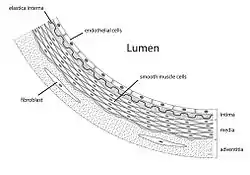

Diagram showing the location of vascular smooth muscle cells. | |

Vascular smooth muscle is the type of smooth muscle that makes up most of the walls of blood vessels.

Structure

Vascular smooth muscle refers to the particular type of smooth muscle found within, and composing the majority of the wall of blood vessels.

Arteries have a great deal more smooth muscle within their walls than veins, thus their greater wall thickness. This is because they have to carry pumped blood away from the heart to all the organs and tissues that need the oxygenated blood. The endothelial lining of each is similar.